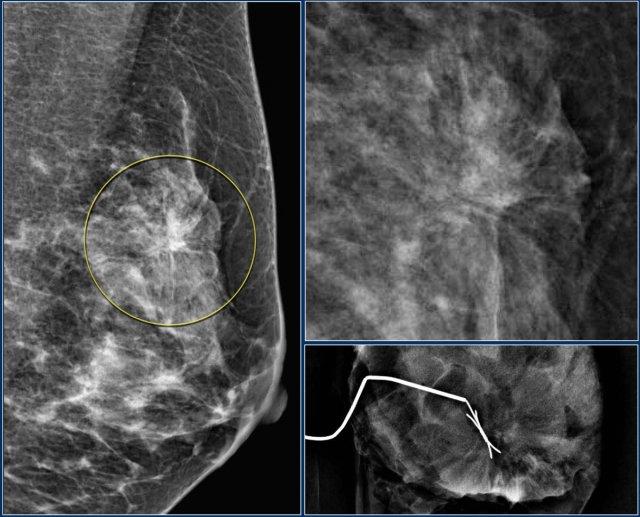

Thuật ngữ biến dạng cấu trúc được sử dụng khi cấu trúc bình thường bị biến dạng mà không có khối rõ ràng nào được nhìn thấy.

Điều này bao gồm các đường thẳng mảnh hoặc các tua gai tỏa ra từ một điểm, và hiện tượng co rút khu trú, biến dạng hoặc thẳng hóa ở rìa nhu mô tuyến.

Chẩn đoán phân biệt bao gồm mô sẹo hoặc ung thư biểu mô.

Biến dạng cấu trúc cũng có thể được ghi nhận như một đặc điểm kèm theo.

Ví dụ, nếu có một khối gây biến dạng cấu trúc, khả năng ác tính sẽ cao hơn so với trường hợp khối không có biến dạng.

Lưu ý sự biến dạng cấu trúc vú bình thường trên tư thế chếch (vòng tròn vàng) và tư thế phóng đại.

Bệnh nhân đã được phẫu thuật cắt bỏ và chỉ tìm thấy mô sẹo trong bệnh phẩm.